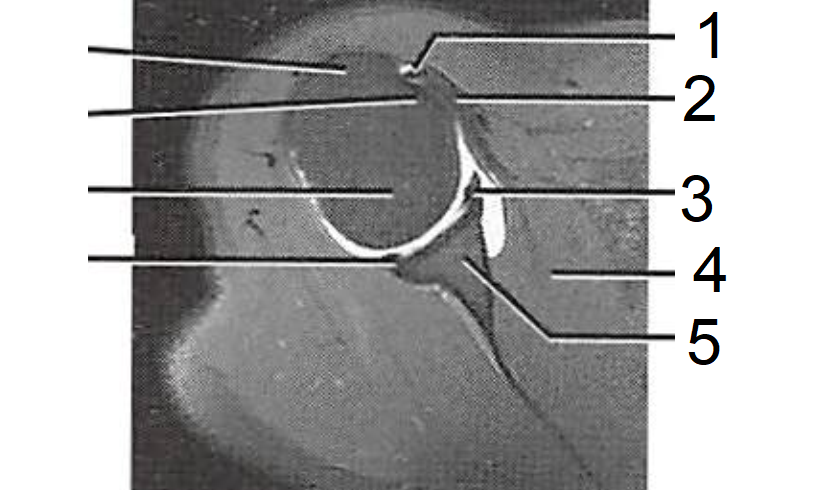

4

1 - Tendão do M. biceps braquial

2 - Tendão do M. subescapular

3 - Lábio articular, anterior

4 - M. subescapular

5 - Cavidade glenoidal